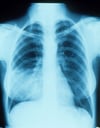

Пневмония в правой средней доле с исчезновением определяющегося контура анатомической структуры на рентгенограмме

Такая рентгенография грудной клетки показывает наличие инфильтрата, который маскирует правую границу сердца (признак "утраты контура"). Признак "утраты контура" указывает на размытое изображение 2 структур, которые имеют похожую рентгенконтрастность; к правой границе сердца примыкает правая средняя доля легкого, таким образом, в этой доле диагностируется наличие инфильтрата и пневмонии.